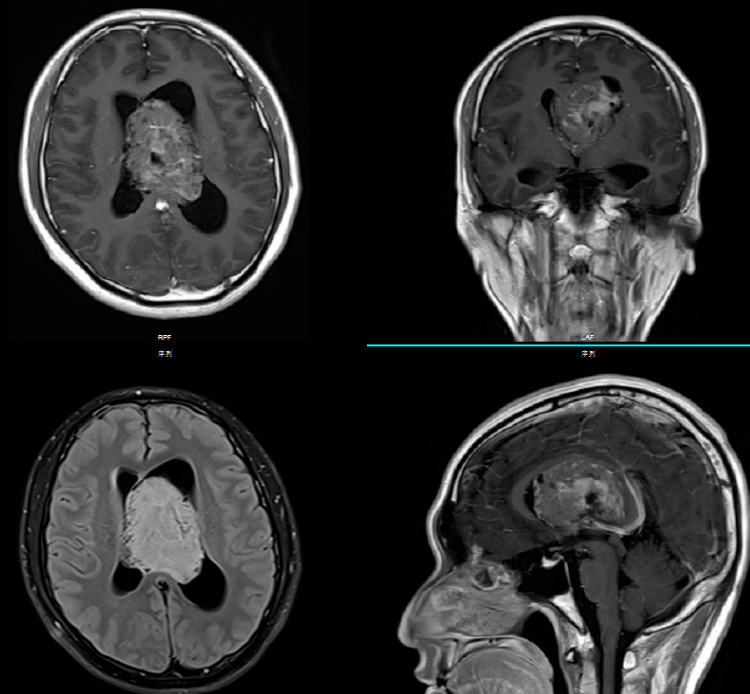

大多数中央神经细胞瘤是多囊性肿瘤且有钙化,以宽基底附着在脑室上外侧壁上。它们通常位于侧脑室或三脑室,附着于室间孔附近的透明隔或脑室壁上。但通常不会出现在侧脑室枕角或颞角。

典型的CT表现是脑室内不均匀的高密度肿块,伴有中等对比增强。MRI T1加权像表现为轻度高信号,T2加权像表现在某种程度上更加多变。使用钆后通常增强。可能难以通过MRI区分中央神经细胞瘤、脑室外神经细胞瘤与更常见的病灶(像高级别胶质瘤)。

较佳治疗方法是完全手术切除。由于这些肿瘤通常再生长缓慢,即使是次全切除也可能延长生存期。典型神经细胞瘤(即MIB-1单克隆抗体检测到生长分数<3%)患者似乎预后,辅助放疗或立体定向放射外科对不完全切除的患者或具有非典型组织学的患者可能有用。对肿瘤复发或进展通常采用局部放疗。至少一项报道提示,复发的中央神经细胞瘤可能对全身化疗有反应。

一项回顾性病例系列研究纳入在35年间使用手术、放疗和/或化疗进行治疗的45例患者,该研究中的治疗结果阐明了中央神经细胞瘤治疗的结局和预后因素。相比病变不典型的患者,典型神经细胞瘤患者的10年生存率(90% vs 63%)和局部控制率(74% vs 46%)更好。术后放疗相比未行术后放疗,术后放疗能够提高患者10年时的局部控制率(75% vs 51%),但这未能转化为总体生存获益。一项纳入71例患者的多中心研究对肿瘤进行了免疫组化评估,结果发现手术程度是的预后指标。然而,该研究的病例数量太少可能不足以确定MIB-1指数的预后阈值。